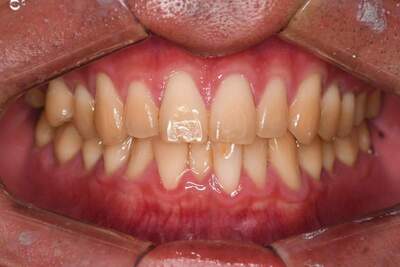

歯列矯正・インレー・クラウン症例

前歯が黒っぽいのが気になる、

悪いところは全部治したい

年齢 54代女性

主訴 歯をきれいにしたい

治療

期間

4年

費用 セラミックインレー 12本

660,000円

オールセラミックプレミアムクラウン 3本

495,000円

矯正 874,900円

計 2,029,900円(税込)

症例写真(治療前)

担当医師所見

治療前:

八重歯が目立ちます。また銀歯もおおく、見た目が気になります。虫歯も散見できます。

症例写真(治療後)

治療後:

矯正治療と虫歯の治療すべて終わったときの写真になります。見た目も最初の頃とは全く違いますし、お口の中もすごく綺麗です。

方針

まずは虫歯の治療を行い、被せ物をする部分は仮歯をいれて矯正を行う。矯正終了後、仮歯の部分を最終的な被せ物に変えていく。また気になっていた銀歯もセラミックに変えて終了となった。

内容

セラミックインレー、オールセラミックプレミアム、矯正